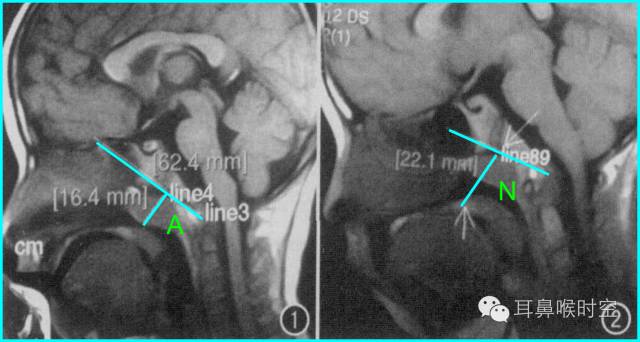

根据经典Fujioka 等 X 线平片测量法原理:

A/ N 比:测量腺样体最大厚度与自硬腭上缘到颅底蝶枕骨的软骨结合部的距离之比

PAS:后气道间隙(pharyngealairway space , PAS)的宽度(软腭表面与腺样体表面之间有效气道宽度)。

采用SE 序列矢状面T1WI

选择正中矢状面,分别测量两条径线(图1、2)

N 线:即从蝶骨体2枕骨斜坡的软骨结合部后缘(O点)至硬腭与软腭上缘交界处的连线N

A 线:过O点沿枕骨斜坡下缘作延长线L,取腺样体下缘最凸点作L线的垂直线。

A/N比:分别测A、N值,计算A/N 比

程万民等 测量:

60例4~14岁儿童,认为

A/N 比≥0.71

PAS≤3mm

为病理性肥大标准和手术指征。